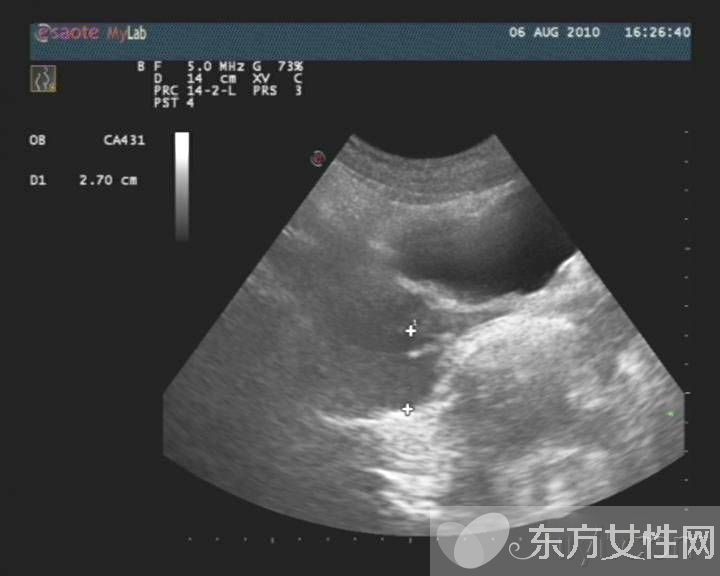

盆腔炎是指女性盆腔生殖器官、子宮周圍的結(jié)締組織及盆腔腹膜的炎癥,主要包括子宮內(nèi)膜炎、輸卵管炎、輸卵管卵巢膿腫、盆腔腹膜炎。

慢性盆腔炎常為急性盆腔炎未能徹底治療,或患者體質(zhì)較差,病程遷延所致。它可使機(jī)體發(fā)生慢性輸卵管炎與輸卵管積水、輸卵管卵巢炎及輸卵管卵巢囊腫、慢性盆腔結(jié)締組織炎。

4、手術(shù)治療有腫塊如輸卵管積水或輸卵管卵巢囊腫可行手術(shù)治療;存在小的感染灶,反復(fù)引起炎癥發(fā)作者亦宜手術(shù)治療。手術(shù)以徹底治愈為原則,避免遺留病灶再有復(fù)發(fā)的機(jī)會(huì),行單側(cè)附件切除術(shù)或子宮全切除術(shù)加雙側(cè)附件切除術(shù)。對(duì)年輕婦女應(yīng)盡量保留卵巢功能。慢性盆腔炎單一療法效果較差,采用綜合治療為宜。

(5)沖任虛寒型:小腹冷痛,喜暖喜按,帶下量多色白質(zhì)稀,畏寒肢冷,舌質(zhì)淡,苔薄白,脈沉細(xì)。常用中成藥內(nèi)服丸劑具有清熱解毒、活血化瘀等作用,可綜合用藥。女性生殖系統(tǒng),任何一方面的疾病都可能引發(fā)盆腔炎,這個(gè)問(wèn)題可大可小,容易導(dǎo)致不孕不育,一定要治療。盆腔積液就是盆腔存在炎性滲出物,可發(fā)生在子宮內(nèi)膜發(fā)炎后,內(nèi)膜組織腫脹的細(xì)胞中滲出的略黏稠的液體,被周圍組織包裹所漸漸形成的囊性包塊。